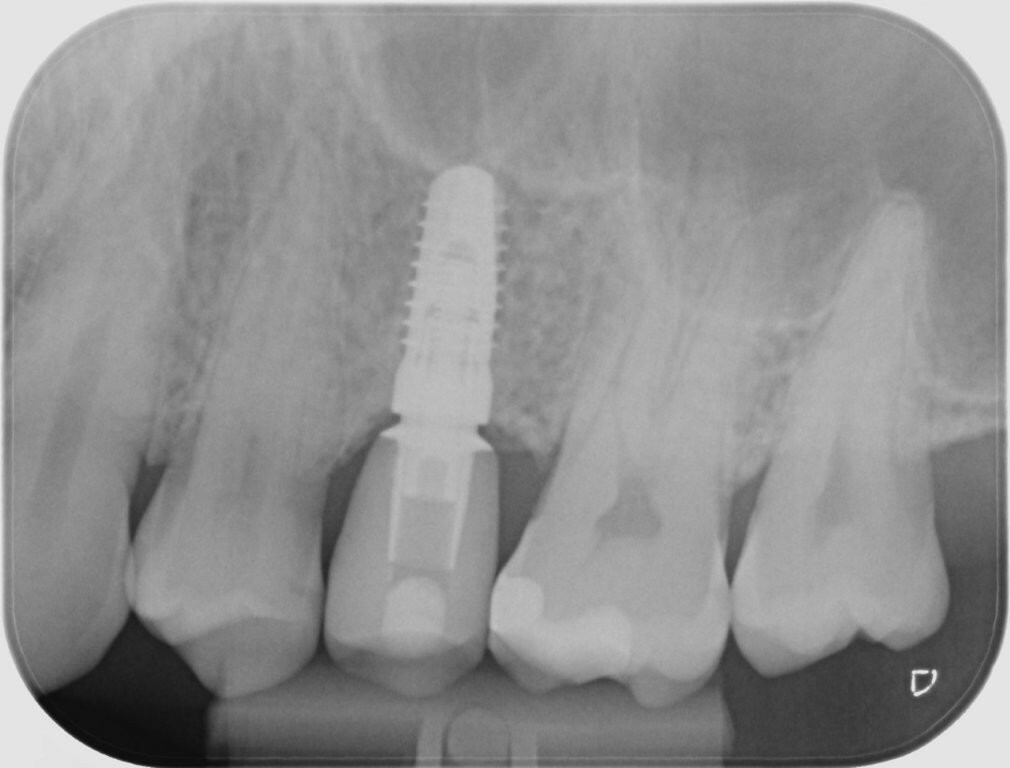

Zu Beginn wurde das Einzelzahnimplantat (Conelog ScrewLine Titanimplantat, 3,8 x 9,0 mm, Camlog) in Regio 25 gesetzt, geschlossen eingeheilt und nach Freilegung mit einem Gingivaformer (Conelog Gingivaformer, wide body, 3,8 x 6,0 mm, Camlog) versehen (Abb. 3). Mithilfe eines VITA-Farbschlüssels (VITA Zahnfabrik) wurde für die spätere Krone die Farbe A3 bestimmt (Abb. 4).